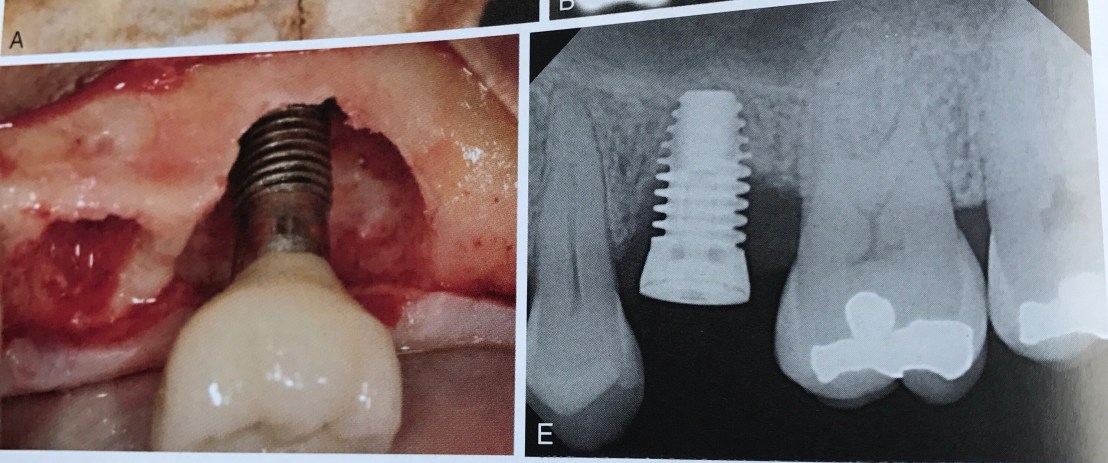

รูปแสดงปัญหาของการวางตำแหน่ง facial มากเกินไปในฟันหน้า

Bone ด้าน facial ไม่พอ ทำให้ attached gingiva ไม่พอไปด้วย นอกจากนั้น Esthetic จาก Prosthesis จะทำได้ยากมาก

การต้องใช้ abutment ทำให้โลหะด้าน facial ต้องถูกกรอตัดออก ความแข็งแรงของ abutment จึงลดลง

Lab จึงต้องชดเชยความแข็งแรงของโลหะด้วยการขยายความกว้างในแนว mesio-distal ทำให้ได้ abutment ที่บานออกมากกว่าขนาด Implant (รูป F ลองสังเกตฐาน metal abutment สีทองกับส่วน Implant สีเขียว)